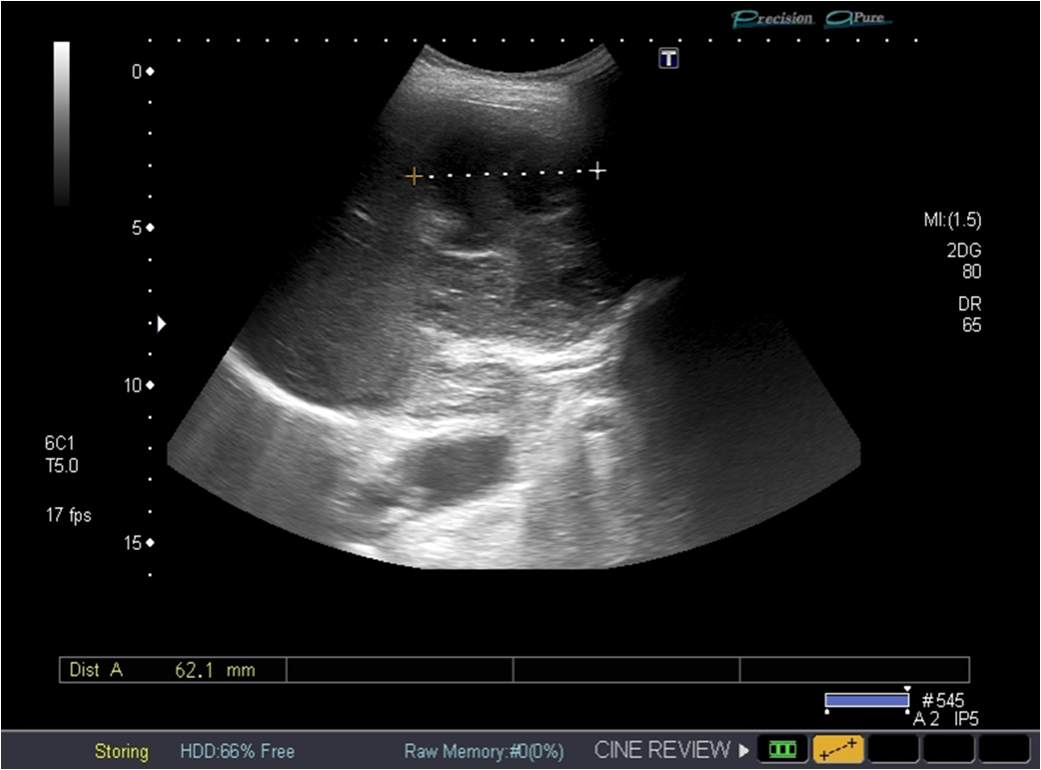

Standard ultrasound showed two oval lesions in the right liver lobe, segment VIII, poorly demarcated, with a mixt complex pattern, a transverse diameter of 7 and 4 cm and another 3,5 cm hypoechoic lesion situated in segment VI. Image guided drainage was performed, with a favourable evolution.